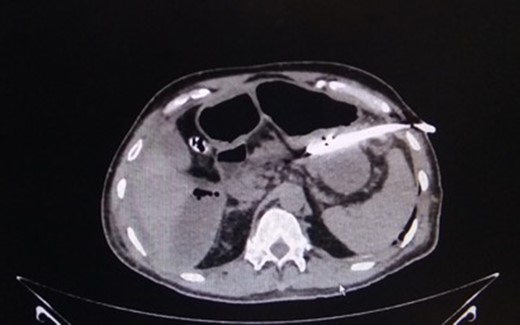

This 50-year-old male had, 4 months previously, undergone an anterior resection of a recto-sigmoid adenocarcinoma, non-anatomical resection of a liver metastasis and diverting loop ileostomy. The pathological report was a moderately differentiated adenocarcinoma and he subsequently received seven cycles of adjuvant chemotherapy. Two weeks after the last chemotherapy cycle he had a contrast study through the distal limb of his ileostomy which was normal. He then underwent a side-to-side hand sewn ileo-ileal anastomotic closure and started passing flatus and stools from the third postoperative day (POD). On POD 4 however he developed lower abdominal distension and a plain X-ray of the abdomen revealed air to be present in the colon and rectum with a few prominent small bowel loops. He then developed massive painless penoscrotal swelling, On local examination the genitals were not tender and there was no elevation of the local temperature (penoscrotal oedema image, Fig. 1). Blood investigations revealed a haemoglobin level of 12.8 g/dl, total leucocyte count of 5900/mm3, serum creatinine of 0.85 mg/dl, total protein 5.18 g/dl and albumin 2.95 g/dl. A urologist’s opinion was sought who opined that the patient might be having common iliac vein thrombosis but a Doppler study of the lower limb and pelvic veins was normal. However the abdominal distension persisted although he was passing flatus and stools. CECT of the abdomen was done on POD-6 and this revealed a large irregular air containing collection extending from the right subhepatic region along the paracolic gutter into the pelvis as well as a fluid collection in the lesser sac extending along the greater curvature of the stomach (CT images). Three percutaneous drains were then inserted—one each in the subhepatic region, pelvis and the left lesser sac and 1500 ml of faeculent content was removed. The patient was kept nil by mouth, started on parenteral nutrition and his antibiotics were upgraded. Over the next 3 days the effluent decreased and the fluid became serous. The penoscrotal oedema also subsided after 4 days (Figs 2–5). On POD-12, a CT scan of the abdomen with oral contrast was done again (CT images), which showed a decreased size of the collection and no well-defined area of extravasation or leak of contrast outside the bowel lumen. The drains were then removed, he was started on oral liquids and later put on a soft diet and discharged on POD-20.

CT-abdomen showing pelvic collection. Source: Department of Radiology, Sir Ganga Ram Hospital, New Delhi.

CT-image of drain in situ draining intra-peritoneal leak contents. Source: Department of Radiology, Sir Ganga Ram Hospital, New Delhi.